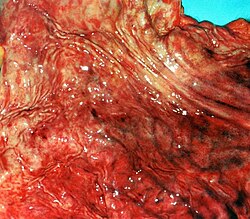

Qastrit — mədənin selikli qişasında iltihabi və ya iltihabi-distrofik dəyişiklikləri ilə müşayiət olunan, adətən uzunmüddətli gedişə malik xəstəliyidir. Qastrit

Qastrit — mədənin selikli qişasında iltihabi və ya iltihabi-distrofik dəyişiklikləri ilə müşayiət olunan, adətən uzunmüddətli gedişə malik xəstəliyidir. Qastrit morfoloji diaqnoz sayılır. Həkim, mədə selikli qişasının bioptatının morfoloji tədqiqatı olmadığı hallarda digər müvafiq müayinələrin nəticələrinə və xəstənin şikayətlərinə əsasən ancaq "funksional dispepsiya" diaqnozu qoya bilər. Qastrit gedişinə görə kəskin və xroniki olar bilər. Qarın nahiyəsində təkrarlanan şiddətli ağrı və qusma appendisitin əlaməti ola bilər. Appendisit çox vaxt qastritlə səhv salınır. Müalicə olunmayan appendisit həyati təhlükə yarada bilər.

• Endoskopik müayinə - qastritə şübhə olduğu vacib müayinə sayılır. Həkim FEQDS ( fibroezofaqoqastroduodenoskopiya ) etməklə acqarına mədə möhtəviyyatının həcmini və xarakterini, mədə selikli qişasının görüntüsünü, rəngini, parlaqlığını, büküşlərin vəziyyətini, mədənin tonusunu və peristaltikasını , ocaqlı dəyişilikləri qiymətləndirir və morfoloji olaraq diaqnozu təsdiq etmək üçün biopsiya götürür. Həmçinin endoskopik müayinə zamanı pH ( turşuluq ) və H.Pylori yoluxmasını da təyin etmək olar .